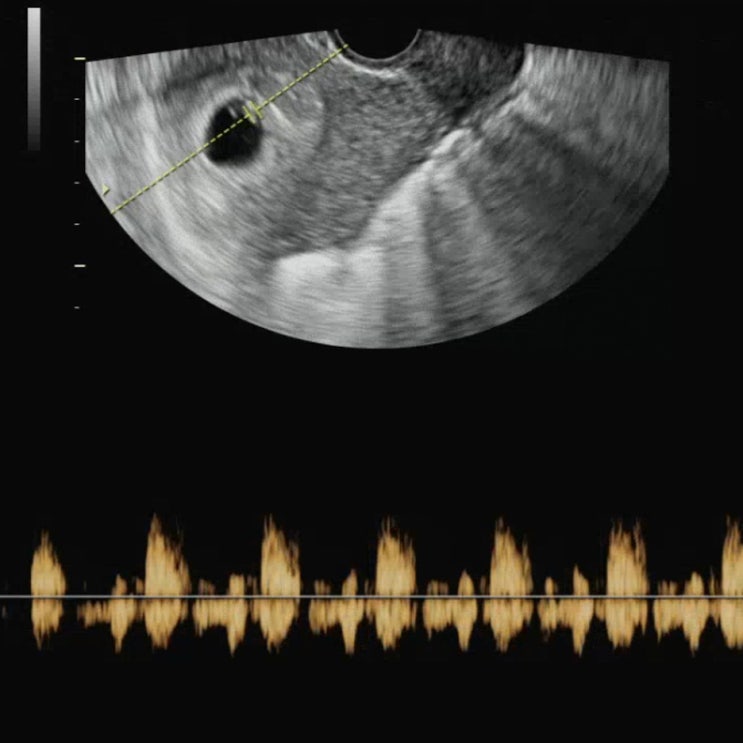

임신 6주차 초음파 심장소리 & 입덧 시작ㅠ

마지막 생리 시작일 : 22년 8월 5일 배란일 : 22년 8월 20일 네이버 주수 계산기 기준 임신 6주차 초음파를...